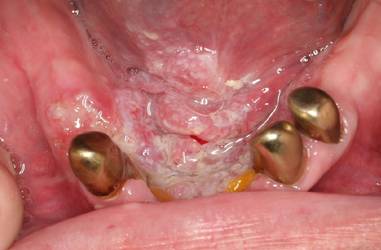

Grundsätzlich gilt: Jede Veränderung der Mundschleimhaut, die länger als 14 Tage besteht sollte ärztlich oder zahnärztlich abgeklärt werden! Das Erscheinungsbild des Mundhöhlenkarzinoms ist vielfältig und reicht vom Vorhandensein vermeintlich harmlos aussehender, nicht abwischbarer weißlicher oder rötlicher Veränderung der Mundschleimhaut bis hin zu offenen Stellen (Ulzerationen) oder Geschwülsten (Gewebewucherungen). Zu Beginn der Erkrankung sind die Veränderungen häufig schmerzlos. Nicht selten deuten Betroffene die Schleimhautdefekte auch als Druckstellen oder Bissverletzungen.